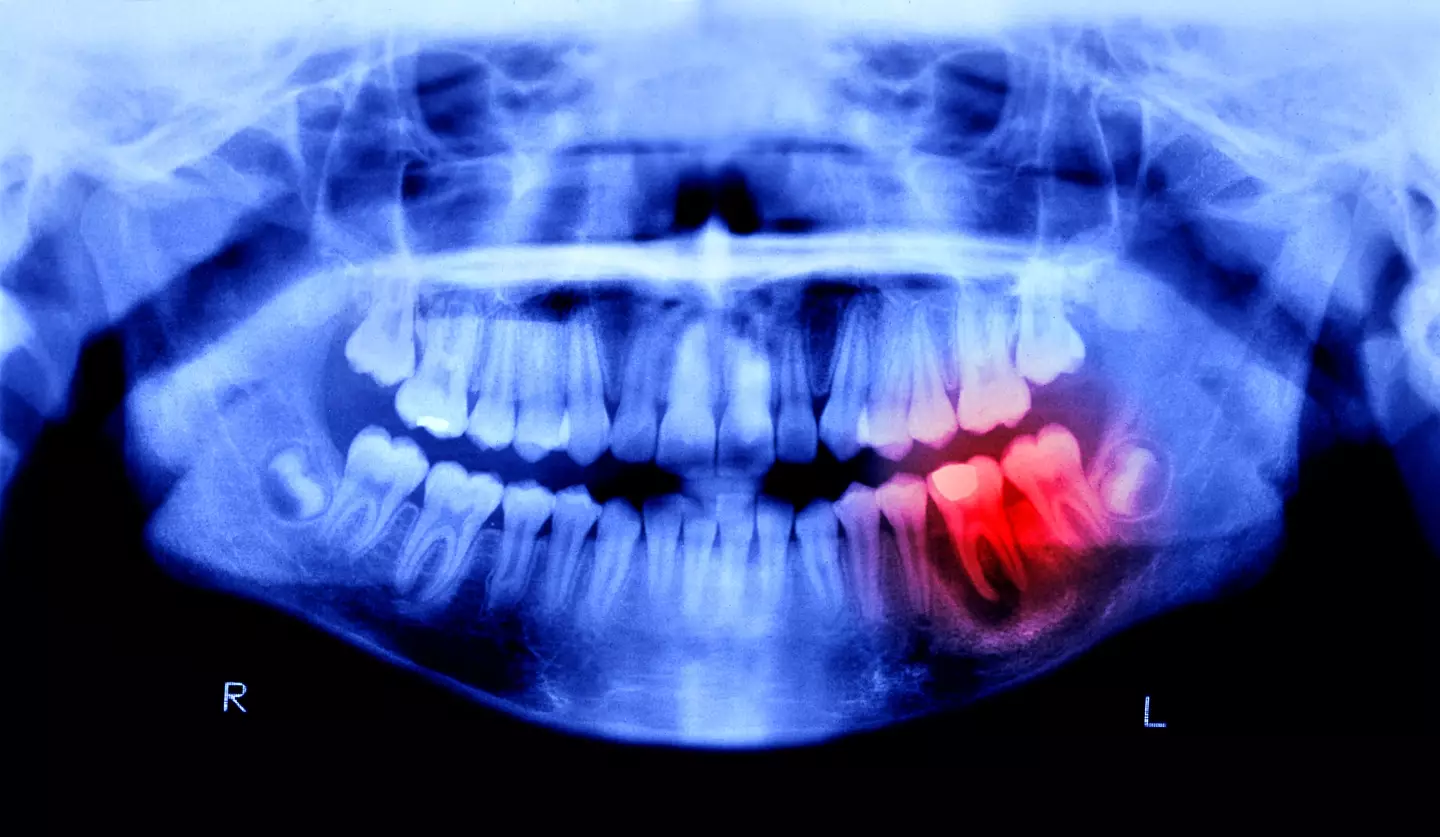

In 2019, a published study found a connection between a common infection in this area and a decline in brain functions - the ailment being gum disease.

According to another paper submitted by University of Louisville microbiologist Jan Potempa, the pathogen behind chronic gum disease (a condition known officially as periodontitis) was also found in the brains of deceased Alzheimer's patients.

According to science alert, previously experiments involving mice found that oral infection with the pathogen (known as Porphyromonas gingivalis) led to brain colonisation.